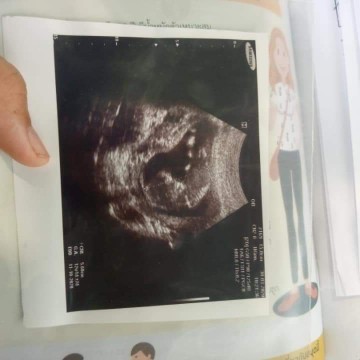

ตอน 13 วีคค่ะ

ตอน12 วีคจ้า